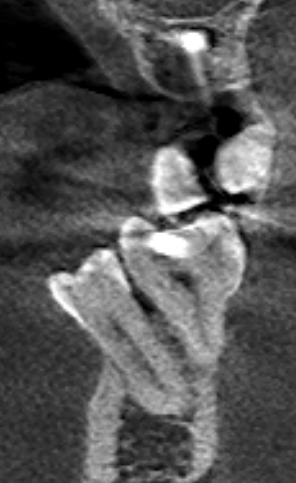

Александр9 Опубликовано 26 ноября, 2021 Поделиться Опубликовано 26 ноября, 2021 Мне предлагают удалить дистопированный 35 зуб, но он мне не мешает. Меня только пугает, что из-за него "страдают" соседние зубы. И если его не удалить, то со временем придется удалять и их. Подскажите пожалуйста, оправданно ли его удаление с целью улучшения "жизни" соседних 34, 36 зубов? (при условии нормальной гигиены (ирригатор, зубные нити) и лечении кариеса). Ссылка на комментарий